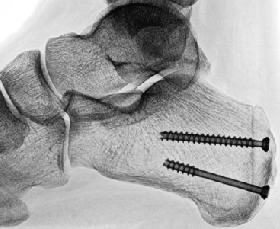

One can employ intraoperative fluoroscopy to confirm that osteotomy exit points match the template. The surgeon can use an osteotomy guide over guide pins to facilitate cuts that are parallel from medial to lateral yet converge at the desired location at the plantar cortex. One would leave the plantar cortex intact for the final greenstick fracture. The strong plantar soft tissues act as a plantar hinge and prevent proximal migration of the posterior fragment in the sagittal plane. Dorsiflexing the foot manually allows the intact Achilles to compress the osteotomy. We used two cannulated cancellous screws to fixate the osteotomy.

Complete healing of the osteotomy occurred 10 weeks after the procedure. We kept the patient non-weightbearing for a period of six weeks with subsequent progressive weightbearing for an additional four weeks. We performed the same procedure six months later on the other foot. No further intervention has been required over the past three years and she has resumed running without symptoms.

There are several advantages to the Keck and Kelly osteotomy. The lateral approach is clear of important structures and limited dissection provides adequate exposure for the dorsally-based wedge osteotomy. The surgeon does not violate the Achilles tendon with this approach. This is the main advantage of this procedure as high-level runners and athletes are generally wary, and often have a preference to avoid any procedure that involves extensive debridement of the Achilles tendon. The osteotomy tilts the posterior calcaneus forward and away from the heel counter, thereby reducing mechanical impingement of the soft tissues in this area. Additionally, the osteotomy slightly elevates the Achilles tendon insertion, which reduces equinus stress that is often a contributing factor to posterior heel pain. Rotation of the posterior fragment also changes the orientation of the Achilles fibers at the insertion point on the posterior heel, which is intended to decrease stress.

Surgeons can achieve fixation with cannulated cancellous screws buried deep to the Achilles or external placement of Steinmann pins. Advantages of pin fixation include a less invasive approach near the Achilles tendon insertion and no residual hardware after removal at six weeks. Advantages of screw fixation include permanent fixation, compression of the osteotomy and no external protrusion of fixation.